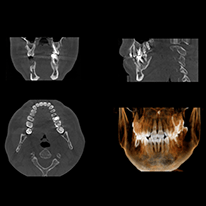

皆様のお口の状態をより精密に検査するため、CT写真を撮影します。

歯科用CTとは

CTとは、コンピュータを使用してデータを処理・画像を再構成、断層写真を撮影することができる装置です。

新しく開発された歯科に特化した最新装置で、より正確な診断に役立つことはもちろん、経過観察などにおいても非常に有効な装置です。

神経損傷などのリスクを回避するために、当院ではCT撮影による精密診断で神経や血管の位置をより正確に把握し、治療計画を立てています。